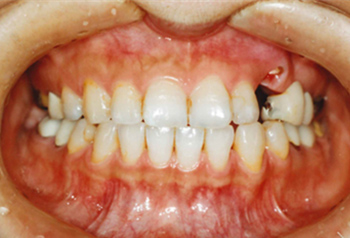

主訴:上顎左側3番を残して欲しい

診断名:上顎左側3番歯肉カリエスにより挺出を行い、上顎左側③4⑤⑥番ブリッジを装着

症状:歯ぎしりがある

患者プロフィール:北九州市小倉北区30代女性

治療方針:上顎左側3番歯肉縁下カリエスにより挺出を行い、上顎左側③4⑤⑥番ブリッジを装着する

治療装置:白い表側矯正装置(マルチブラケット)

抜歯:非抜歯

治療期間:約6か月

説明したリスク副作用:痛み・治療後の後戻り・歯根吸収・歯髄壊死など